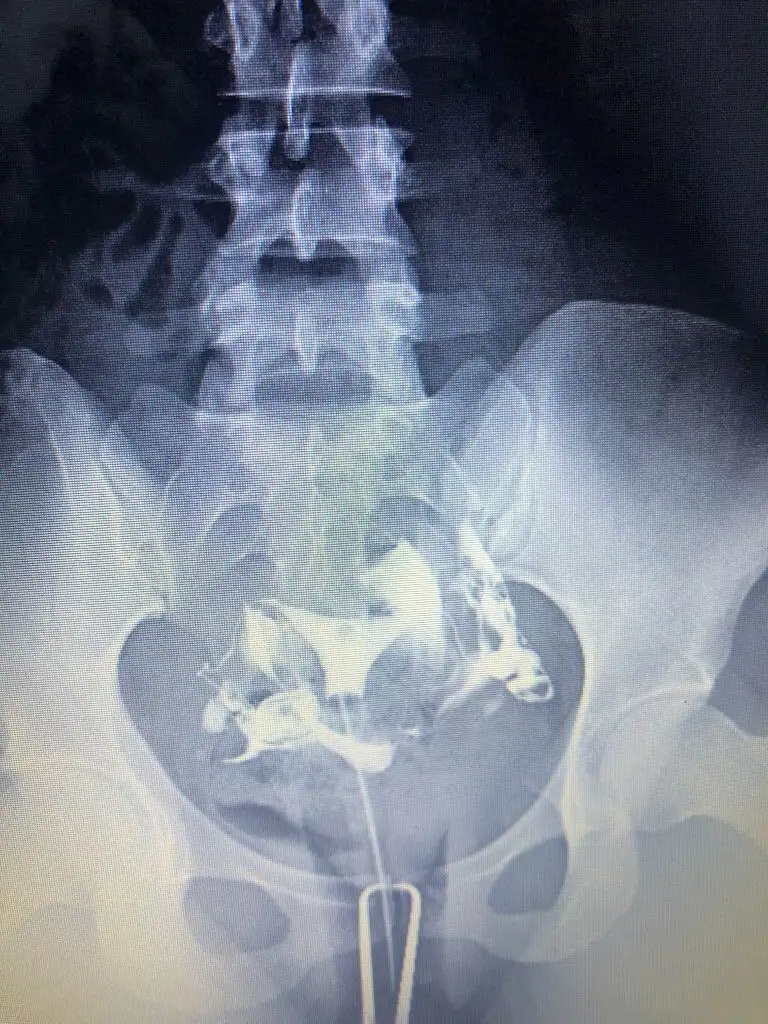

Cok teşekkür ederim.Nasil atabilirim bir bakayim cd de aldim görüntüyü yarin bilgisayardan atmayi deneyeyim bir. Kuşku birakan nedir nededi doktor.ben iki farkli doktora gittim ikiside ayni yorumu yapti. Sıvı dolu olan tüp bosaltilsa bile tekrarlama riski yüksek yani bu demek oluyor ki bosaltilr tüpü denedik bebek yapmayı olmadi herşey basa saracak tekrar hsg cekilecek kapandi mi diye gibi. Bu nedenle sıvı dolu tüpün alınması ortak karardi. Diğer tıkalı olan tüp ise hsg cekilirken doktorum zaten acmaya calismisti açılmamışti ameliyat sırasında da ilk oncelik onu açmaya calismak oldu ama geride bir dermoid kist (ameliyat sırasında görülebildi) tüpü tikamis ve acmays çalıştiklarinda tüpe basinc nedeniyle zarar vermis oyuzden oda alındı.İyi dileklerim sizinle

Özelden hsg görüntünüzü bana atar mısınız sakıncası yoksa ben iki kere çekildim normal raporlandı ama bir doktor aklımda kuşku bıraktıbu yüzden araştırma içine girdim, iki aşılamam negatif oldu

Ben Funda hanıma görselleri attığımda problem olduğunu düşünmüyorum dedi, ben çok fazla doktora gittim Çünkü bir neden bulunamıyordu yalnızca biri hidroselpenks dedi ve laparoskopi önerdi ben de o an çok şaşırıp çıktım. O yüzden bu durumu yaşayanlara mutlaka soruyorumCok teşekkür ederim.Nasil atabilirim bir bakayim cd de aldim görüntüyü yarin bilgisayardan atmayi deneyeyim bir. Kuşku birakan nedir nededi doktor.ben iki farkli doktora gittim ikiside ayni yorumu yapti. Sıvı dolu olan tüp bosaltilsa bile tekrarlama riski yüksek yani bu demek oluyor ki bosaltilr tüpü denedik bebek yapmayı olmadi herşey basa saracak tekrar hsg cekilecek kapandi mi diye gibi. Bu nedenle sıvı dolu tüpün alınması ortak karardi. Diğer tıkalı olan tüp ise hsg cekilirken doktorum zaten acmaya calismisti açılmamışti ameliyat sırasında da ilk oncelik onu açmaya calismak oldu ama geride bir dermoid kist (ameliyat sırasında görülebildi) tüpü tikamis ve acmays çalıştiklarinda tüpe basinc nedeniyle zarar vermis oyuzden oda alındı.

Benimkine hic benzemiyorBen Funda hanıma görselleri attığımda problem olduğunu düşünmüyorum dedi, ben çok fazla doktora gittim Çünkü bir neden bulunamıyordu yalnızca biri hidroselpenks dedi ve laparoskopi önerdi ben de o an çok şaşırıp çıktım. O yüzden bu durumu yaşayanlara mutlaka soruyorum

Ben İzmir’de değilim ama bir ayağım İzmir’de bu yüzden medikal aklımda olan bir yerdi buna istinaden kendisi ile yazıştım.Benimkine hic benzemiyorhidrosalpkinks diyen hangi doktor. Benim hsg cekimini yapan doktor Mehmet Bal ameliyatimida o yapti. Ama Funda hocaya hsg filmlerini göstermiş , Funda hanima o yolendirdi beni zaten. Ben bir de Engin Sarıca' ya gittim hsg raporumu götürdüm inceledi oda ayni yorumda bulundu

Yani acikcasi benimkini hatırladığım kadariyla ve simdi google dan baktığım diger örnek hidrosalpkinksler gibi degil görüntün yani bende boyle şiş bir yer gorunuyordu resmen. Hsg cekilirken ağrın oluyor mu ? Mesel ben tupleri acik olanlarda cok agrisi oluyor diye duymadim. Ben agridan mahvolmuştm ki anestezili cekilmeme rağmen. Bence normal gibi görünüyor tüplerin ama güvendiğin bir doktor varsa ve sartlaro cekimi iyi olan bir yer agrinda olmuyorsa için rahat etsin diye tekrar cektirebilirsin. Ama bence hic gerek yok bir kaç doktor ayni yorumu yaptiysa eğerBen İzmir’de değilim ama bir ayağım İzmir’de bu yüzden medikal aklımda olan bir yerdi buna istinaden kendisi ile yazıştım.